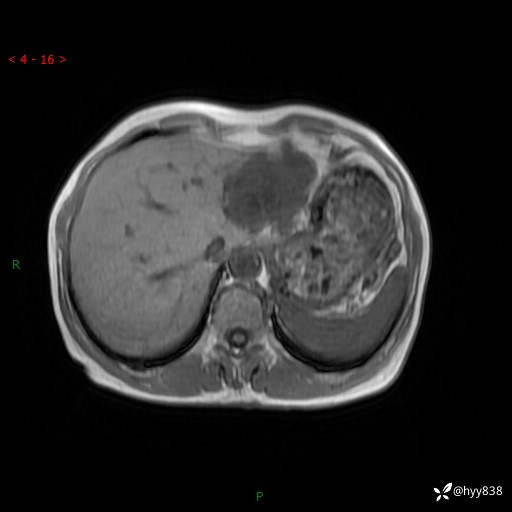

老年女性,偶然发现肝脏占位,综合各个序列,你考虑什么---结果公布

主诉:发现肝脏占位性病变2天

简要病史:患者2天前因“腰疼”至当地医院就诊时发现肝脏左叶占位性病变,无发热、畏寒,无皮肤黄染,无腹痛、腹泻,无恶心、呕吐、厌油等不适,今进一步诊治遂来我院就诊,门诊以“肝脏占位性病变性质待查”收入我科。 起病以来,患者精神、睡眠一般,饮食欠佳,二便正常,体力、体重无明显减轻,

临床诊断:肝占位

肝脏MRI平扫(同反相位)

T2WIfs+DWI

增强(动脉期+静脉期+延迟期)